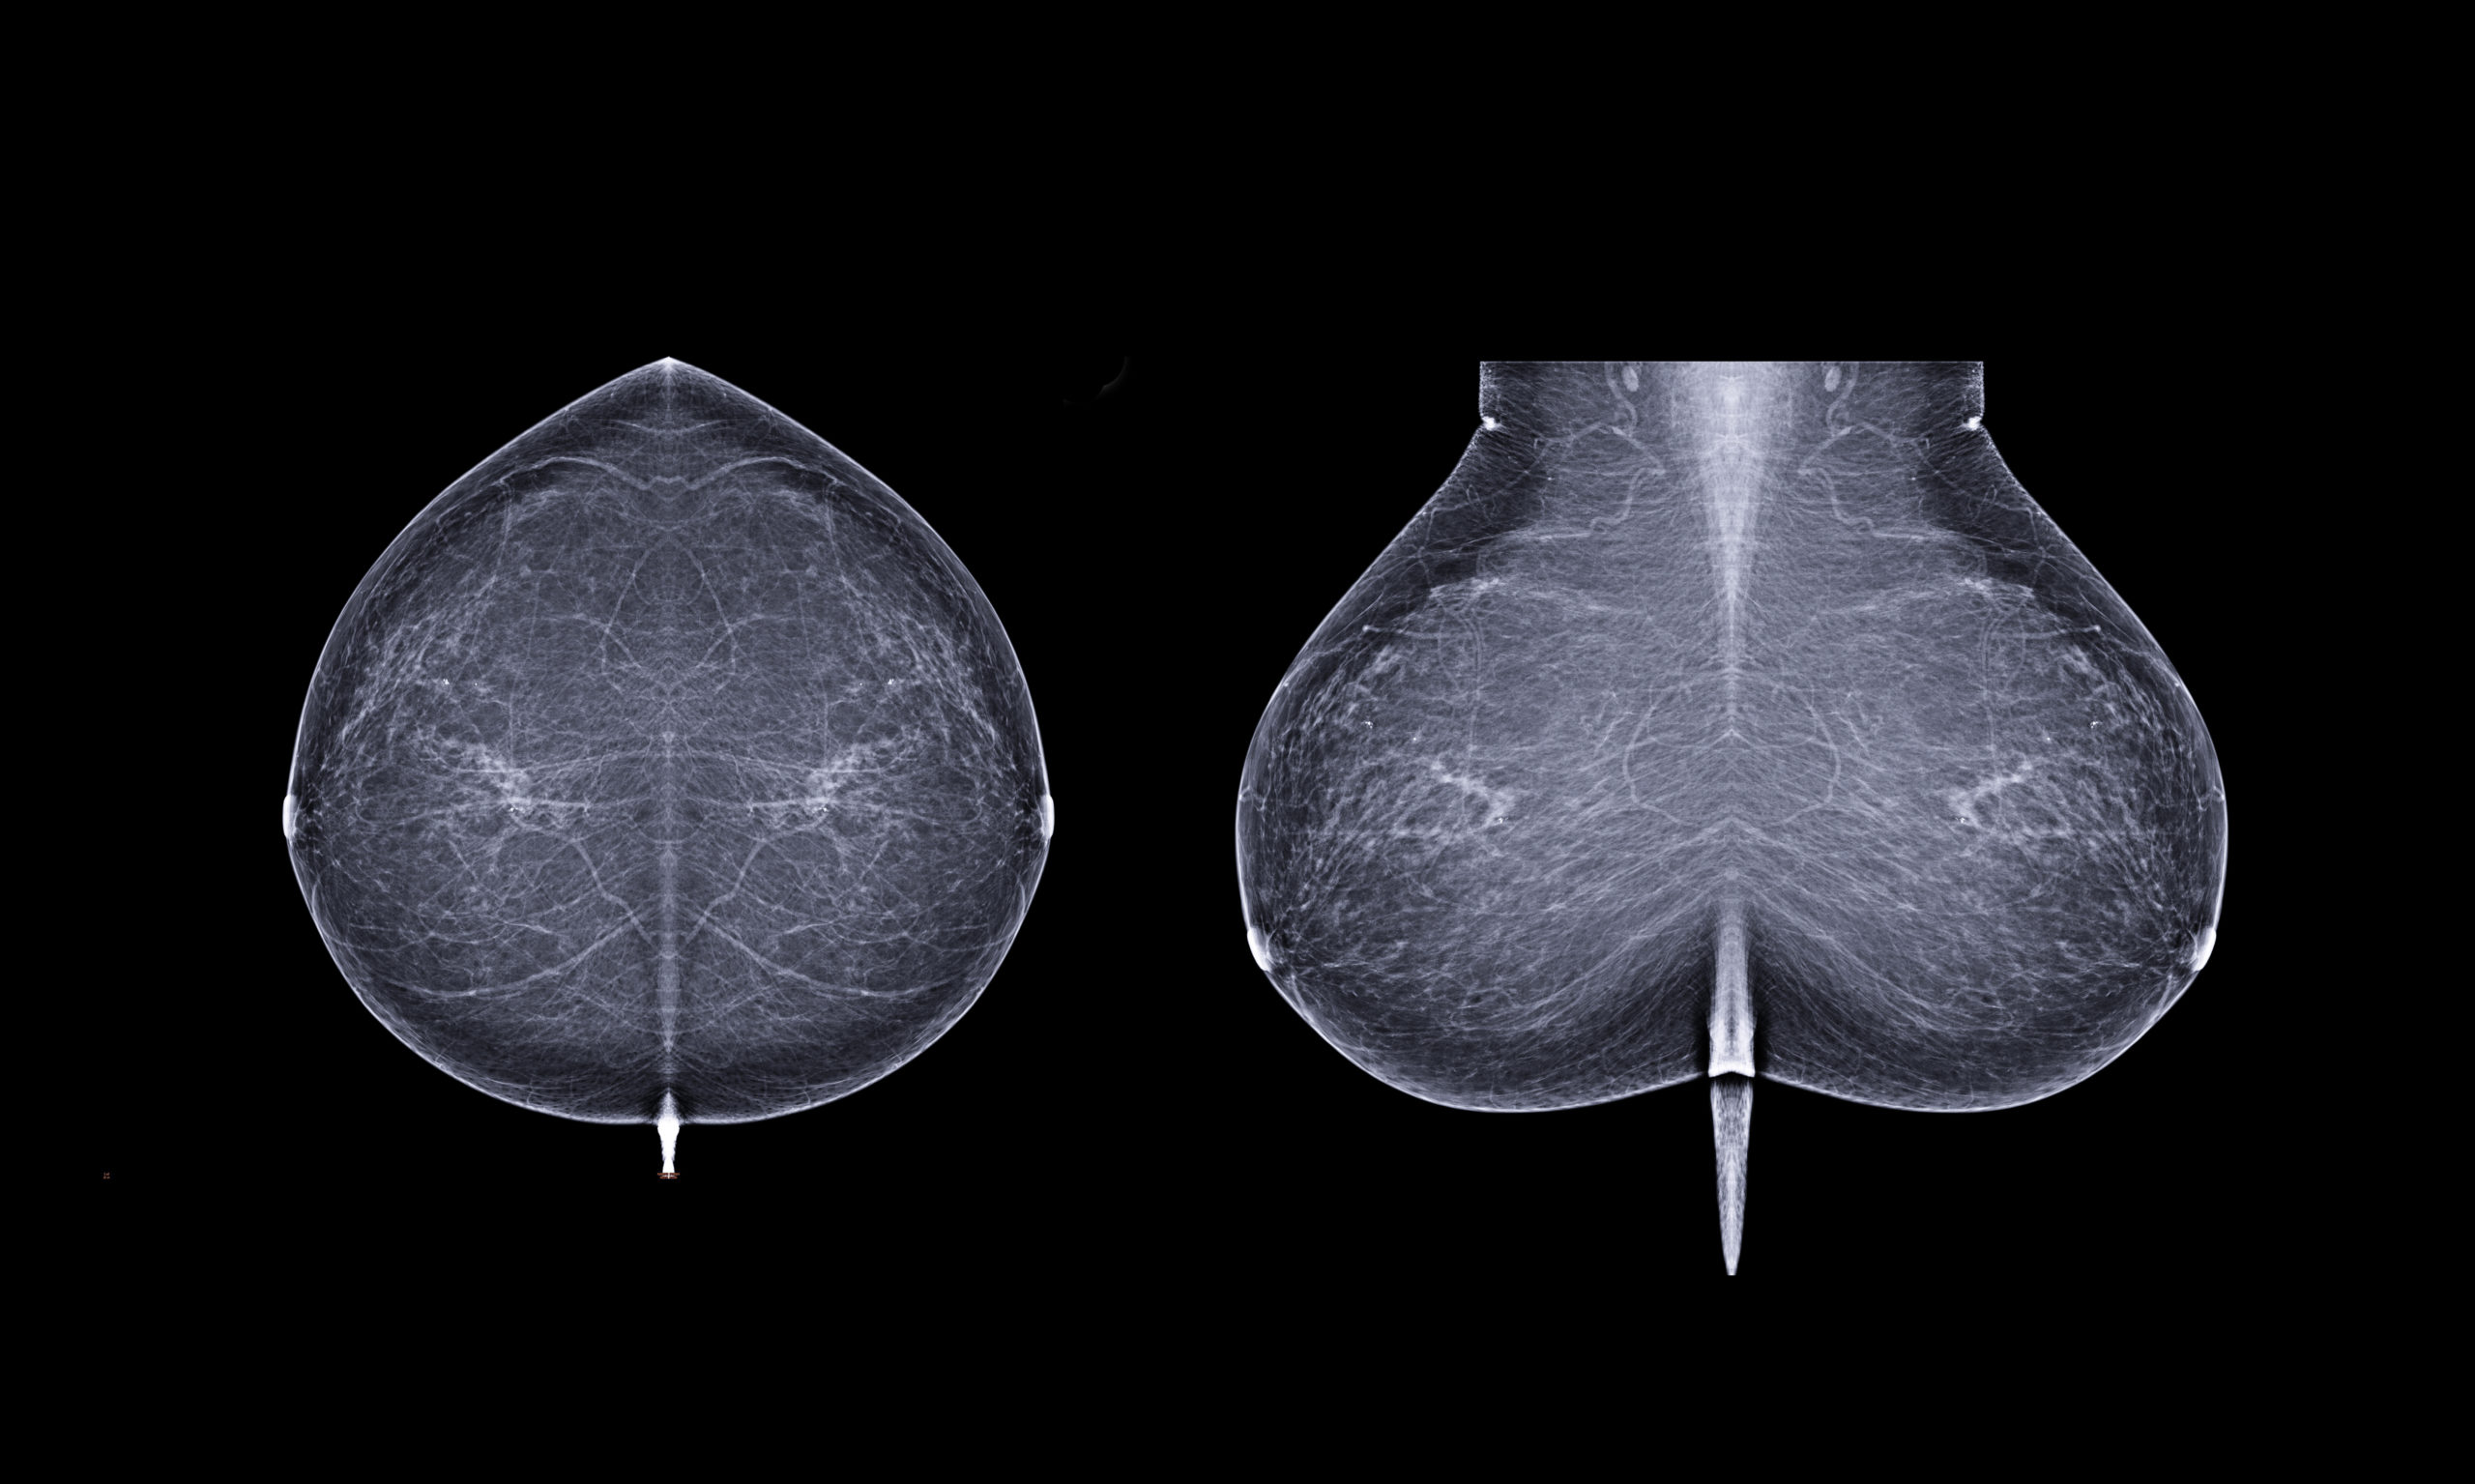

Mammographie

L’exploration radiologique du sein la plus courante est la mammographie. Celle-ci peut être associée à une échographie et à une ponction.

La mammographie est une radiographie des seins.

La mammographie consiste à prendre différents clichés de la poitrine de la patiente, généralement un de face et un en oblique sur chaque sein. Afin de réaliser ces images de coupes, le sein est placé entre deux plaques qui compriment le sein durant quelques instants. C’est durant ce laps de temps que les clichés radiographiques sont réalisés.